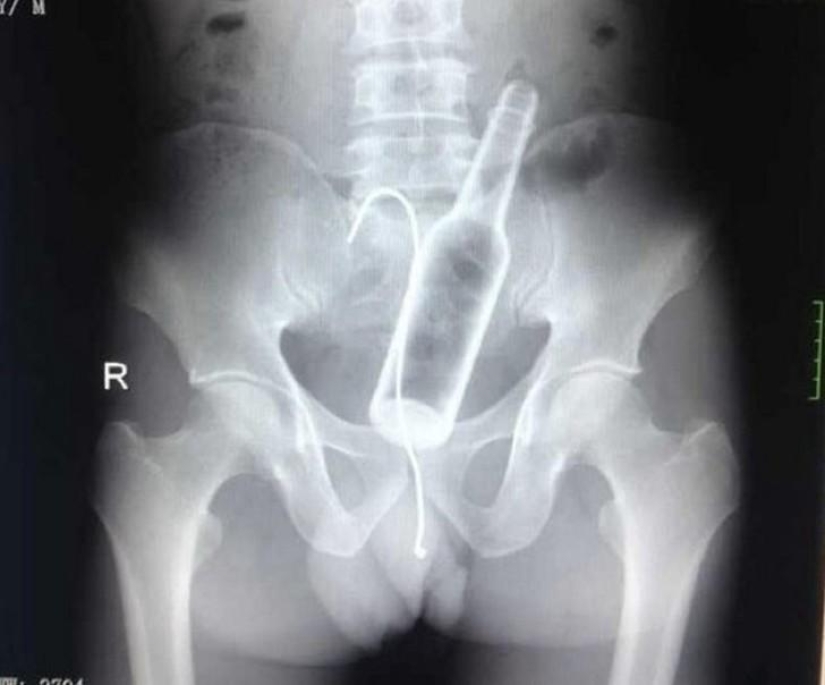

Botella.